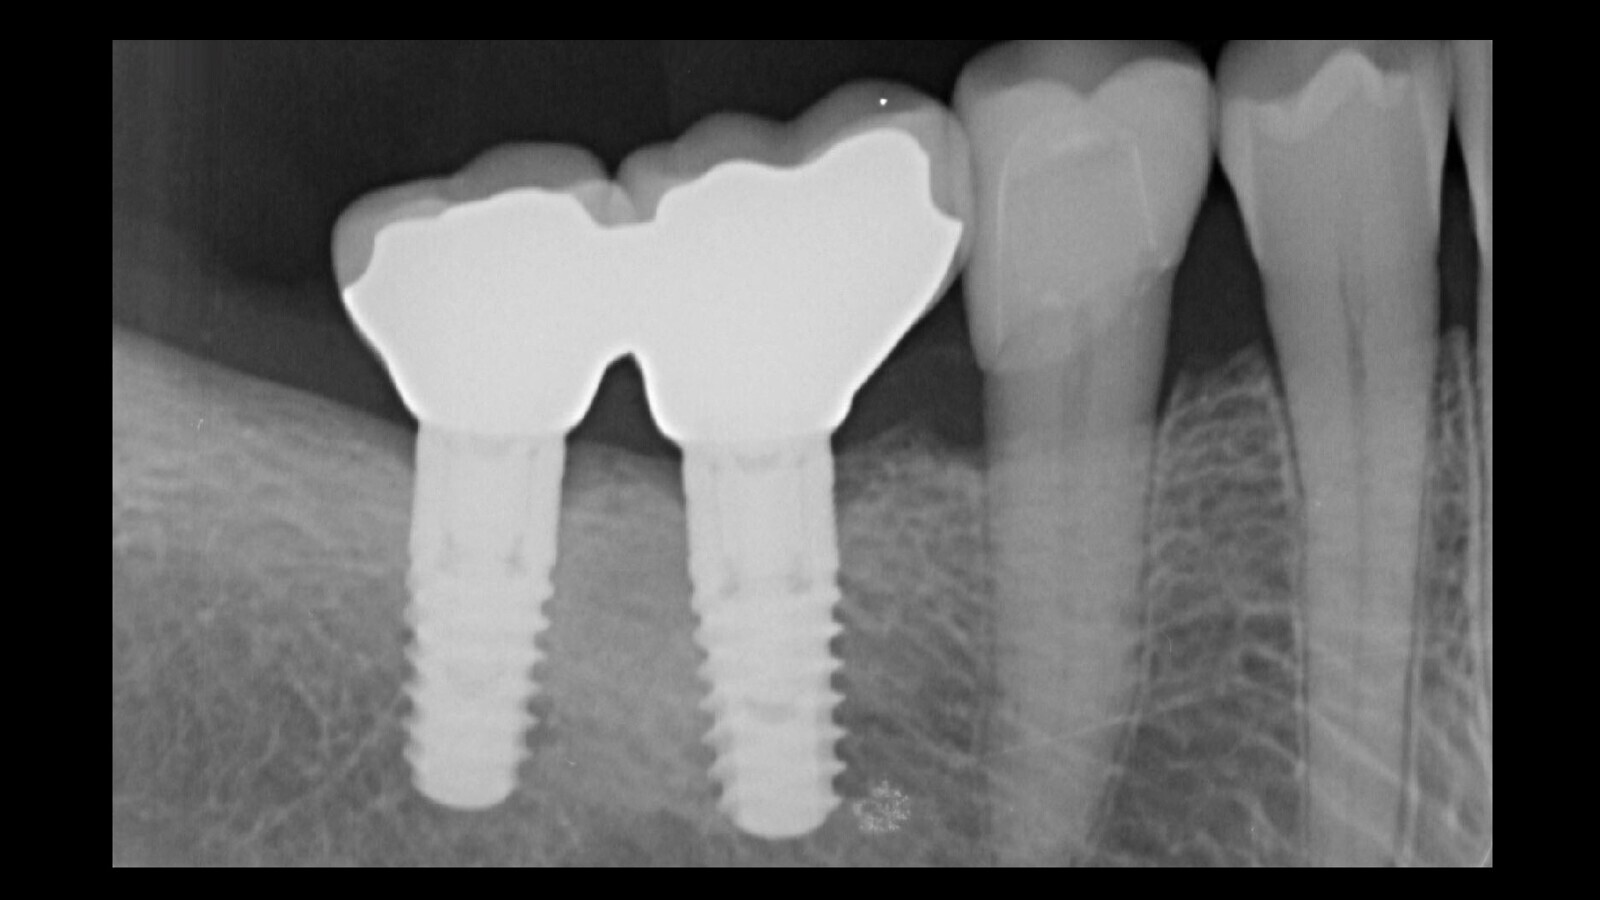

Figura 2. La presencia de un solo tornillo con la cabeza con el encaje para el destornillador y la integridad del relleno del orificio de acceso oclusal en el elemento 4.6 sugería que el segundo tornillo estaba fracturado. De lo contrario, el artefacto protésico no podría haberse desprendido.

Figura 3. Esta intuición fue confirmada por el examen radiográfico, que mostró claramente el fragmento del tornillo separado dentro del implante.